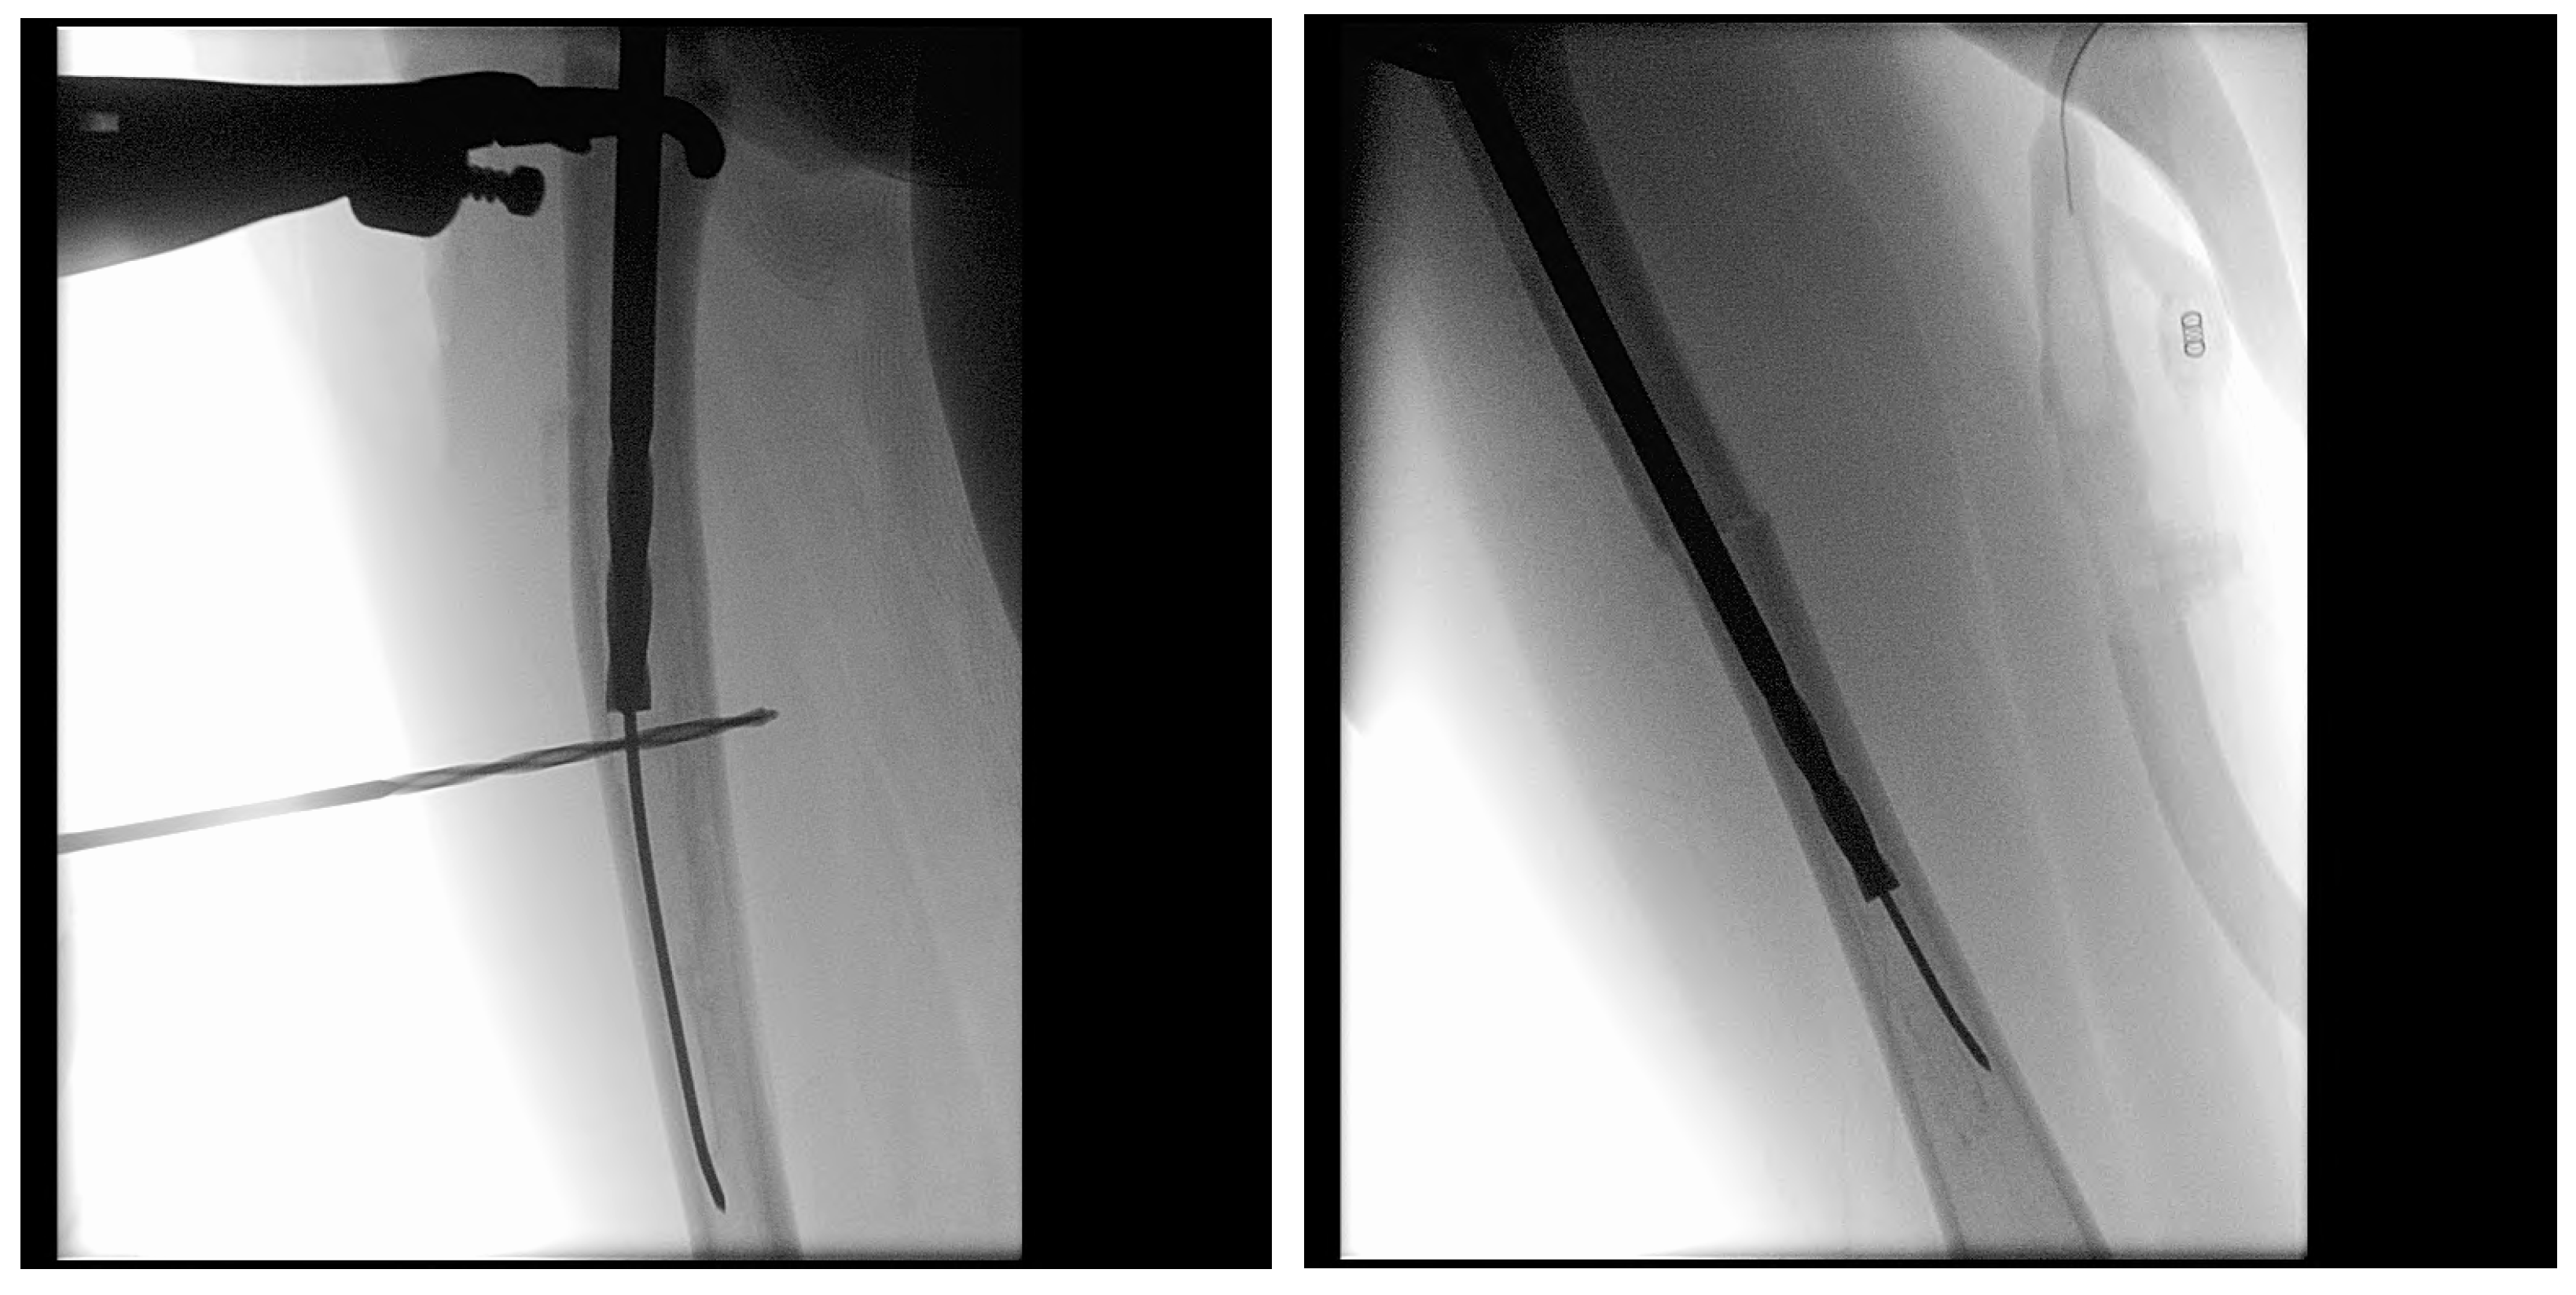

Figure 9.

(A–H): Series of intraoperative fluoroscopy images demonstrating insertion of the SLIM nail. (A) After osteotomy, the fracture is reduced. (B) Lateral view of proximal reaming through the osteotomy site. (C) AP view of proximal reaming through the osteotomy site. (D) Lateral view of distal reaming through the osteotomy site. (E) AP view distal reaming through the osteotomy site. (F) Insertion of the SLIM nail. (G) SLIM nail is gradually advanced past the osteotomy site. (H) AP view of installed SLIM nail, with proximal threading in the epiphysis.